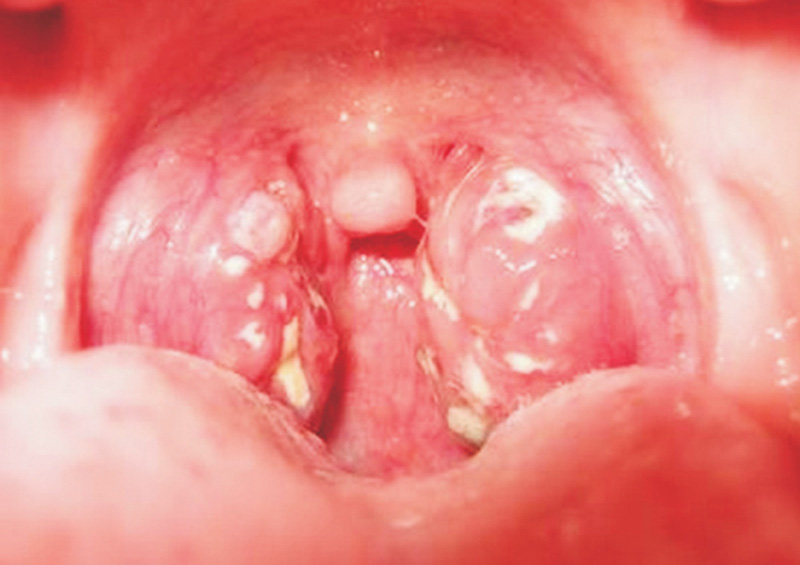

Bệnh nhân là em Đinh Văn N. (7 tuổi, trú thị trấn Di Lăng, huyện Sơn Hà). Em N. đến khám tại Trung tâm Y tế huyện Sơn Hà trong tình trạng sốt cao, mệt mỏi và đau họng.

Sau khi chẩn đoán mắc bệnh bạch hầu, N. được chuyển xuống Bệnh viện Sản - Nhi tỉnh Quảng Ngãi và đang được điều trị tích cực ở khu vực cách ly, phòng lây nhiễm cho các bệnh nhi khác.